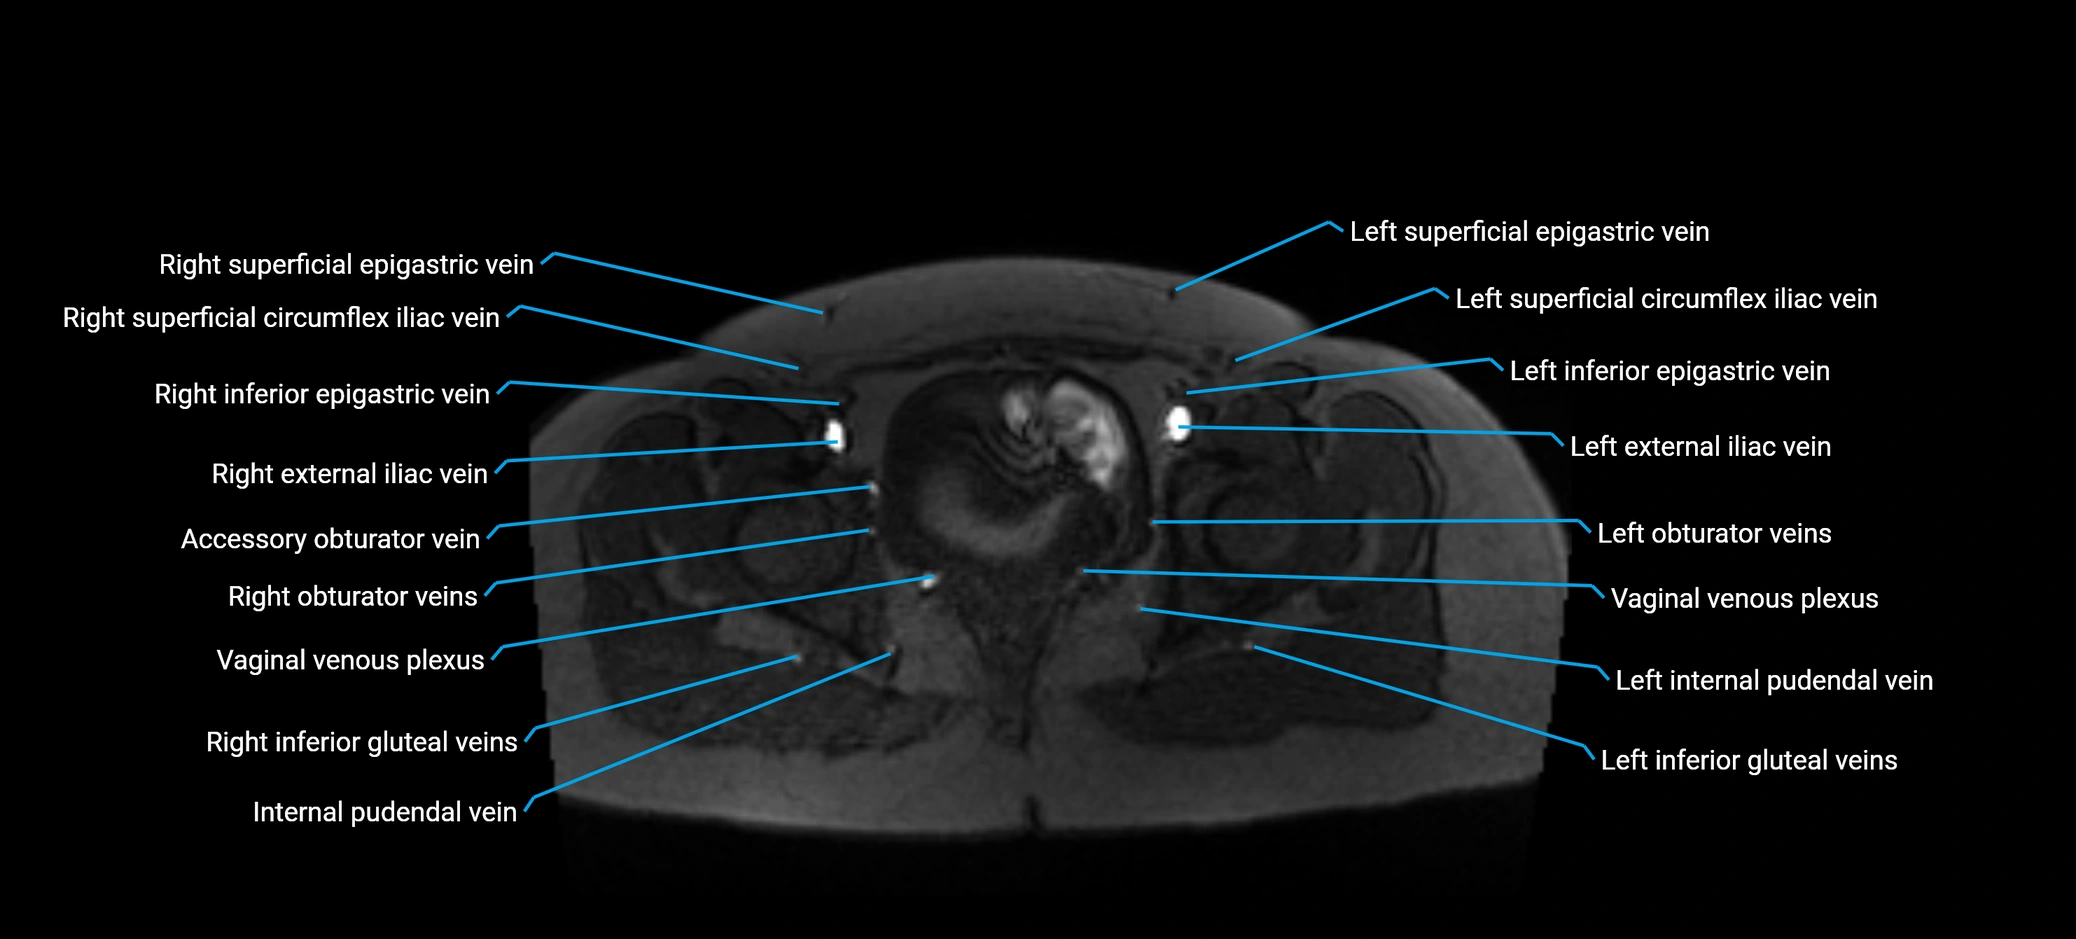

MRI image

image